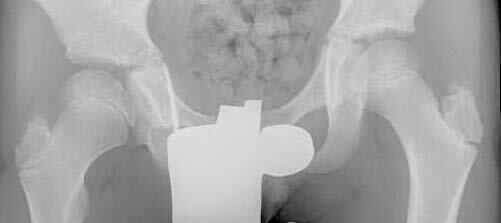

Example of Hip Distraction Treatment

Eleven-year-old boy with late-onset Perthes disease. He previously underwent a shelf procedure at another institution that failed.

X-ray shows the hip during hip distraction. Note that the femoral head is completely contained inside the hip cup.

These X-rays show the hip one year after hip distraction treatment. The hip has full range of motion, and the boy is not in pain.What are some of the logistical issues for children undergoing hip distraction treatment?